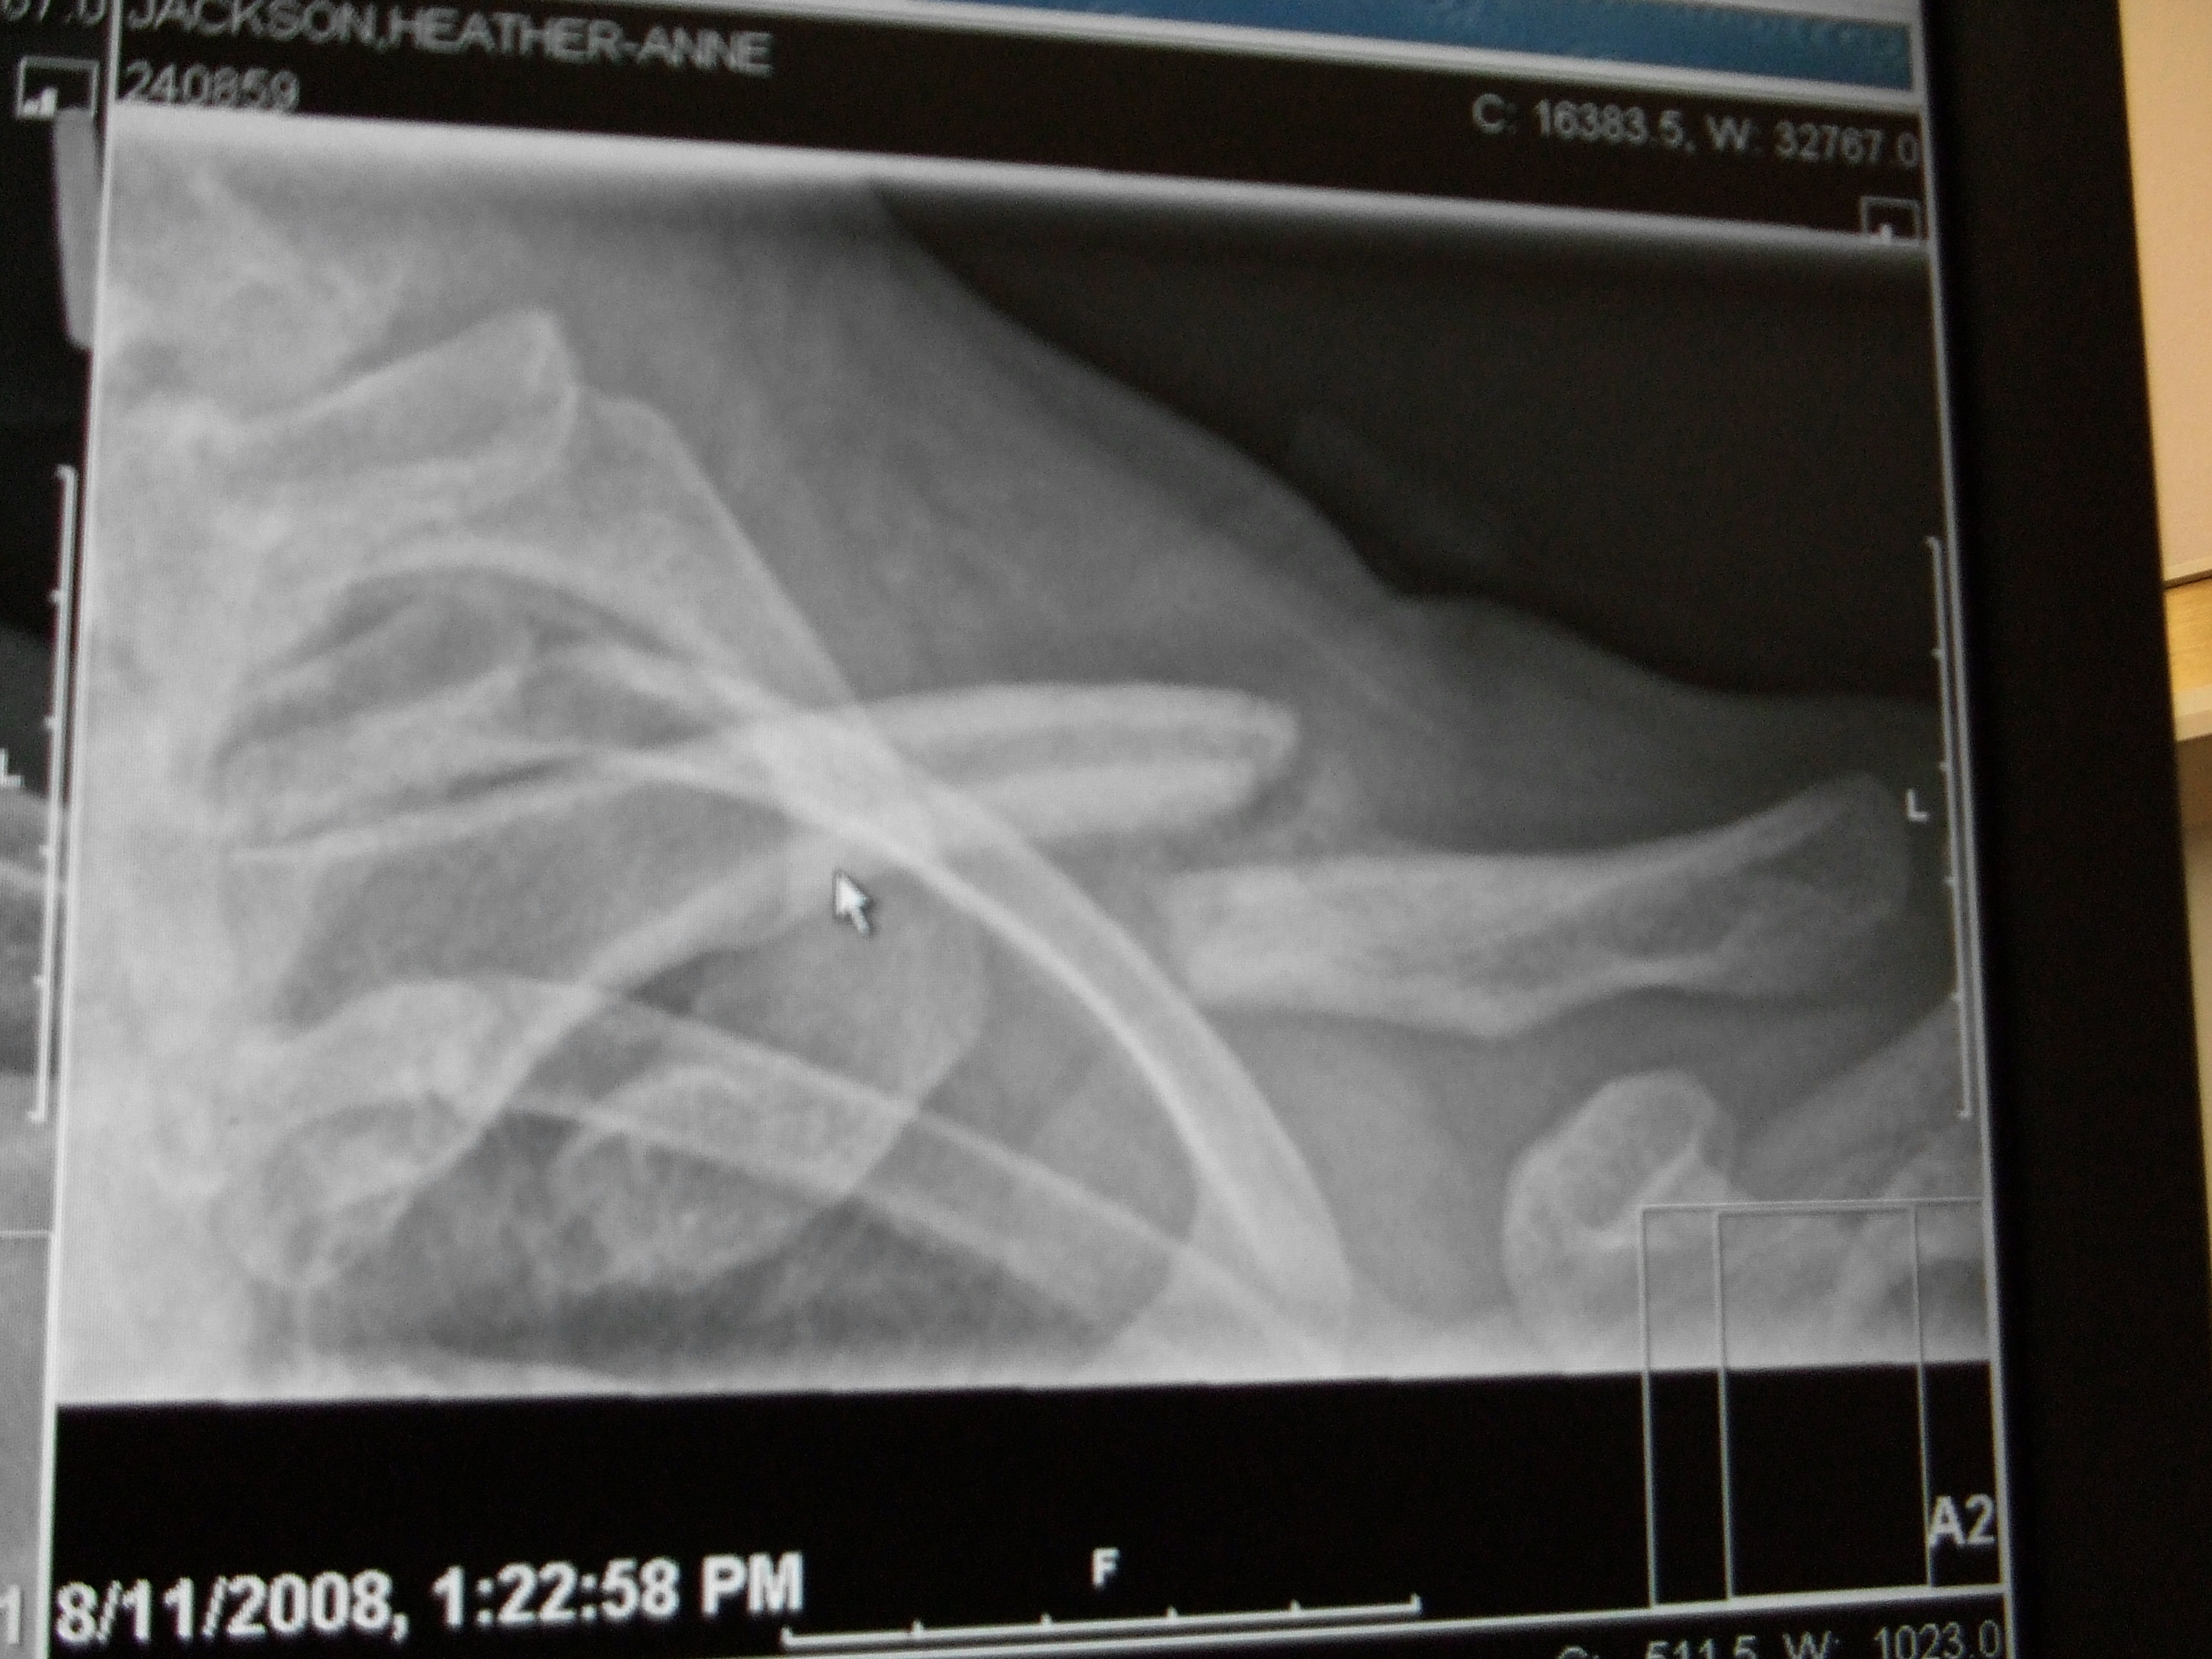

New X-ray's from August 11th, 2008. Apparently the "fluffy" stuff in between the bones is the bone healing. The doctor said it will take another 3 months to heal properly. 2 down, 3 to go...